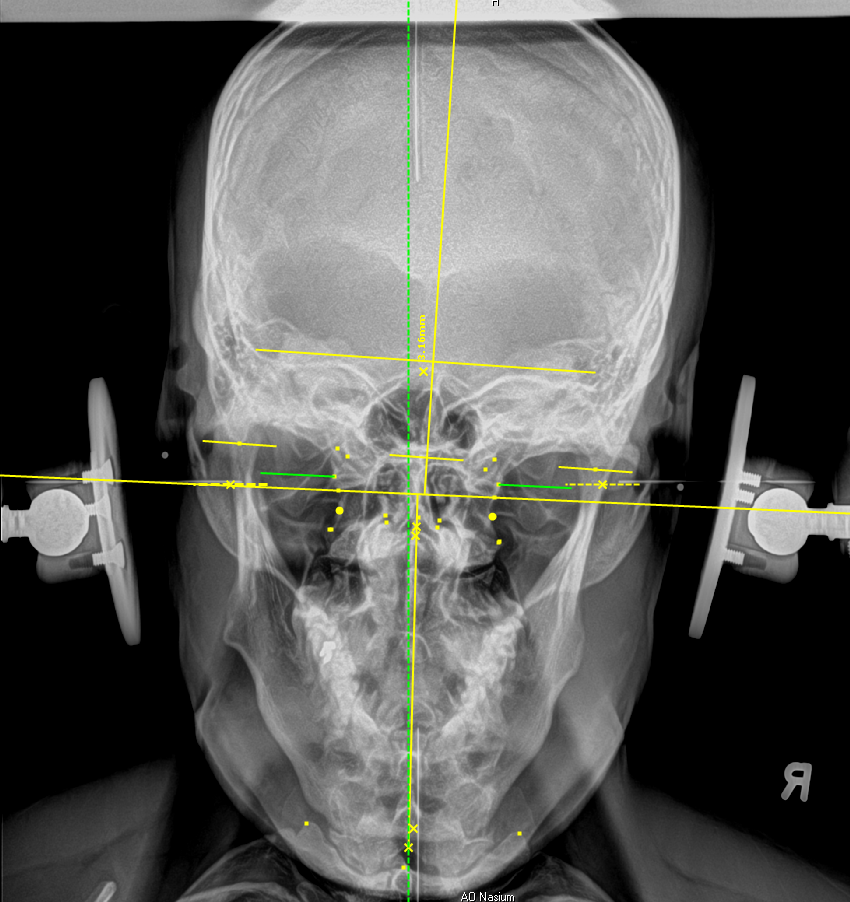

Trust in the expertise of Optimum Chiropractic. As a NUCCA Level 2 provider, we utilize advanced techniques, including highly detailed X-rays, to measure precise changes in atlas alignment. Driven by a dedication to excellence, we have been practicing NUCCA for 11 years. Our commitment to your well-being is further underscored by five years of training with one of the country’s top authorities in this field. Our credentials speak to our commitment to providing you with the highest standard of care.

Advanced Diagnostic Tools

We utilize state-of-the-art diagnostic tools, including detailed X-rays, to understand the precise changes needed in your atlas alignment. This technology ensures accuracy in your treatment plan.